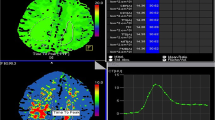

Tracking Therapeutic Intervention Prespasmolysis and Postspasmolysis

In Fig. 3, we present serial TTP measurements, including measurements before and after spasmolysis at day 10. In the cohort, four patients underwent a spasmolysis. All these patients showed a significant reduction of the TTP measurements (9.62-s delay vs. 6.07-s delay, p = 0.043) comparing prespasmolysis with postspasmolysis (Fig. 3a). Our data confirmed that normalized TTP values were more robust in tracking the effects of spasmolysis across multiple examinations (Fig. 3b).

Analysis of TTP values in patients before (red) and after (green) spasmolysis (a). TTP values show a significant decline after spasmolysis. b Comparison between normalized (red) and nonnormalized (gray) TTP values in one patient (patient #1) before and after spasmolysis. Normalized values show a clear decrease in TTP values at day 10 after spasmolysis, which was indicated because of a new neurologic deficit. In contrast, nonnormalized values don’t reflect the effect of spasmolysis on TTP values. TTP, time to peak, UPI, ultrasound perfusion imaging